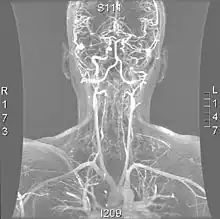

| Arteries of the neck, with arrows indicating the right vertebral artery | |